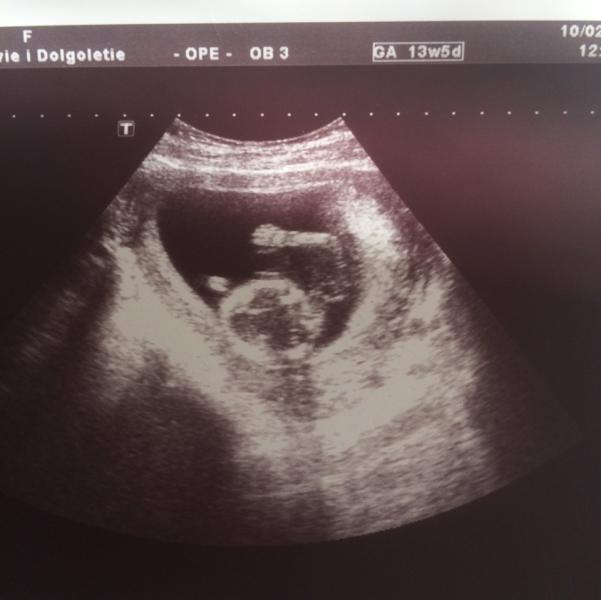

Была на первом скриниге, вот такие мы 🤗 много эмоций) Хочу посоветовать неплохую клинику Здоровье и Долголетие. Мне её здесь тоже посоветовали. Все понравилось и врач и процесс. Сказала все по делу, что нужно на этом сроке посмотрела, сделала мне две фотографии бесплатно. И само узи стоит всего 850 р

Отличная такая фотка. Малыш машет ручкой, типа:" Привет, родители!"